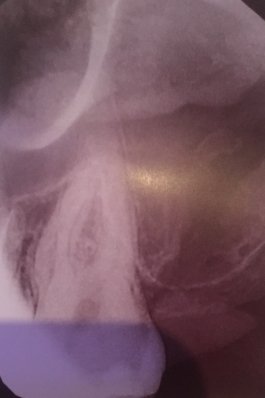

Здравствуйте! Есть ли у меня киста? Если да, то как срочно нужно делать операцию и как она называется?